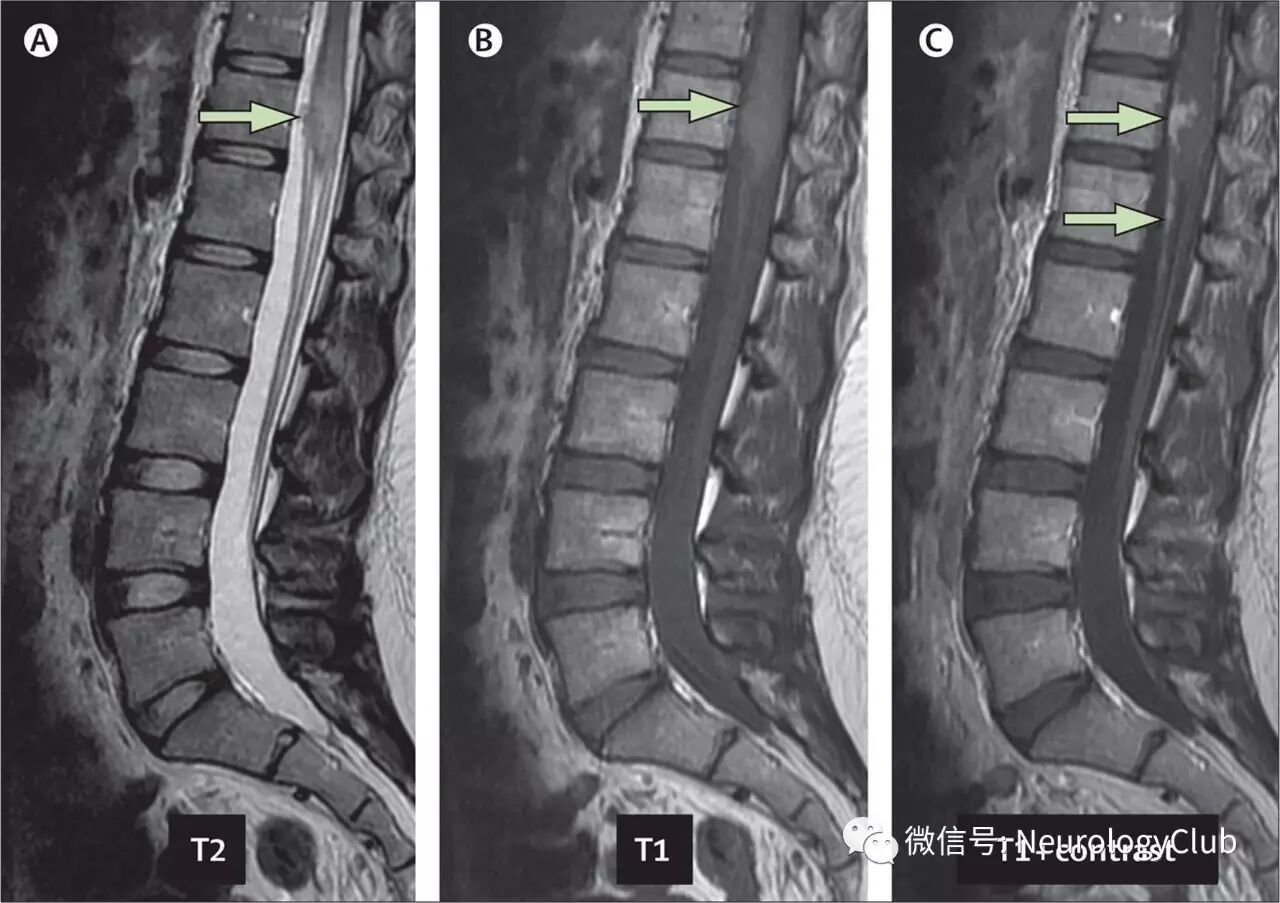

(图:T2WI[A]和T1WI[B]可见水肿的脊髓圆锥[箭];增强后[C]可见结节样强化)

辅助检查:脊髓MRI见圆锥水肿,增强示马尾强化及圆锥结节状病灶,考虑肿瘤或肉芽肿性病变。腰穿仅蛋白轻度增高(0.88g/L)。其他常规的血液生化检查无特殊。偶尔一次血常规发现嗜酸性粒细胞轻度增多(600/ mm3 注:正常<400/mm3,即0.4×10^9/L)。